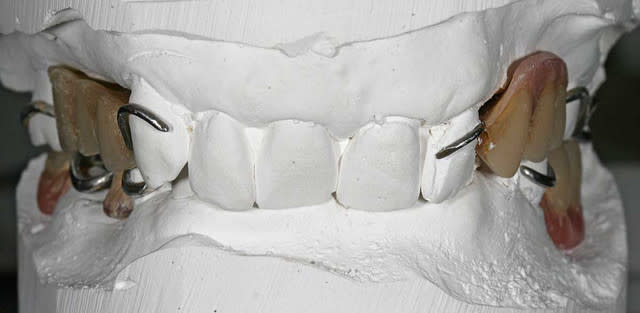

j'avais posté deux photos des modèles sans prothèse

voici les modèles prothèses en place

je précise que la 46 est bien présente, je l'ai cassée sur le platre

Modèle face yuu003 - Eugenol